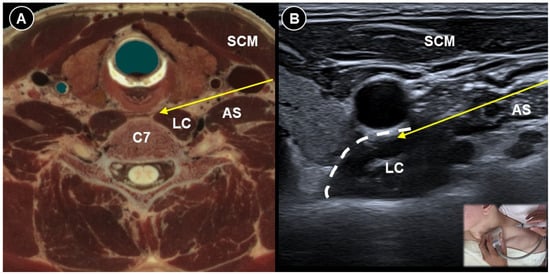

| Acute herpes pain | Burning, stabbing, or itching pain in the affected dermatomal distribution | Reactivation of VZV leading to viral nerve damage and inflammation | Cervical: supine, head turned to contralateral side Thoracic: prone | Cervical:

| Reduce pain and lower postherpetic neuralgia incidence by TPVB/ESPB (meta-analysis), PRF/SNRB/SGB (RCT) |

|

| Post-herpetic neuralgia | Persistent pain after rash resolution | Central and peripheral sensitization | Effective pain control by PRF (RCT), TPVB/SNRB/brachial plexus block/SGB/PNS (case study) | |||